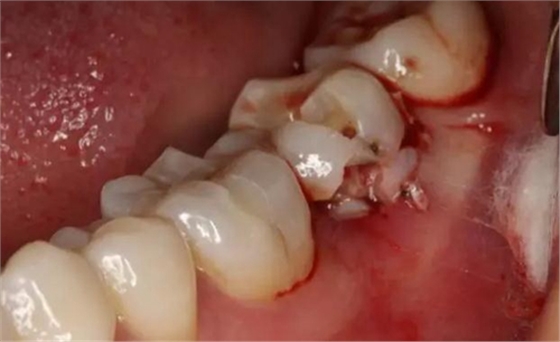

圖6.微創(chuàng)挺拔除37。

圖7. 37牙冠碎裂。多生牙壓迫吸收程度嚴(yán)重。